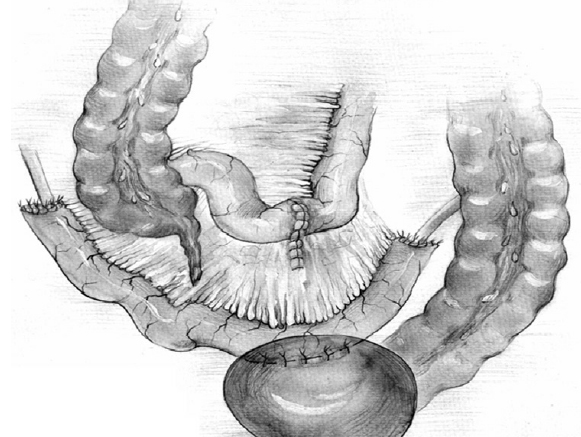

Bilateral small intestinal reconstruction of the ureters was performed in 40 (20.7%) patients. Most often, in 24 (60.0%) patients, U-shaped ileoureteroplasty was performed (Figs. 8 and 9), and more complex reconstructions were performed less often; that is, Y-shaped in 1 (2.5%) case, J-shaped in 3 (7.5%), L- and 7-shaped (Figs. 10 and 11) ileoureteroplasty in 6 (15.0%), and that with two separate ileografts in 6 (15.0%) cases.

Fig. 8. Bilateral U-shaped ileoureteroplasty

Bilateral ileoureteroplasty is a more complex and traumatic surgical procedure. Most often, the need for the procedure arises in case of radiation damage to the urinary tract. Partial or complete replacement of both ureters can be performed simultaneously or in stages using one or two separate segments of the bowel. The staged approach to surgery depends on the severity of the patient’s condition and destructive changes in the urinary tract. Bilateral ileoureteroplasty becomes more complicated because the length of the ureteral sections requiring replacement increases. This is due to (1) a wide and traumatic surgical approach; (2) the need to exclude a more extended segment from the small intestine; (3) the inclusion of a long convoluted segment(s) of the intestine into the urinary system, which leads to a larger area of resorption and an increased risk of metabolic disorders; and (4) the abovementioned complicated aspects of plastic surgery of the right ureter in the isoperistaltic position.